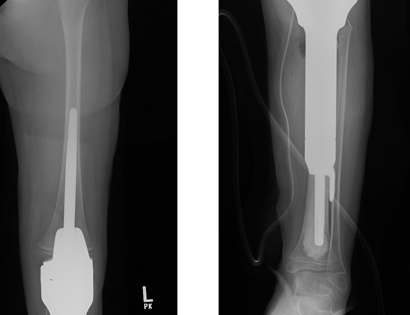

Proximal Tibia X-ray

This is an x-ray image of the tibial prosthesis post-surgically.